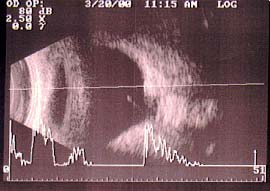

À Ultrassonografia pode-se observar condensações vítreas e aumento grande da escavação papilar deslocada posteriormente.

Ultrassonografia olho direito